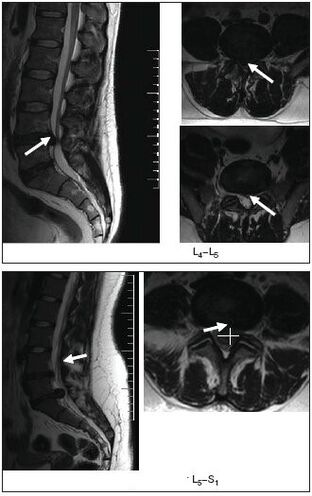

risonanza magnetica

Risonanza magnetica Un metodo diagnostico altamente accurato che aiuta a visualizzare i cambiamenti più piccoli. Aiuterà a fare una diagnosi sia in fase iniziale che in casi complessi prima del trattamento chirurgico.